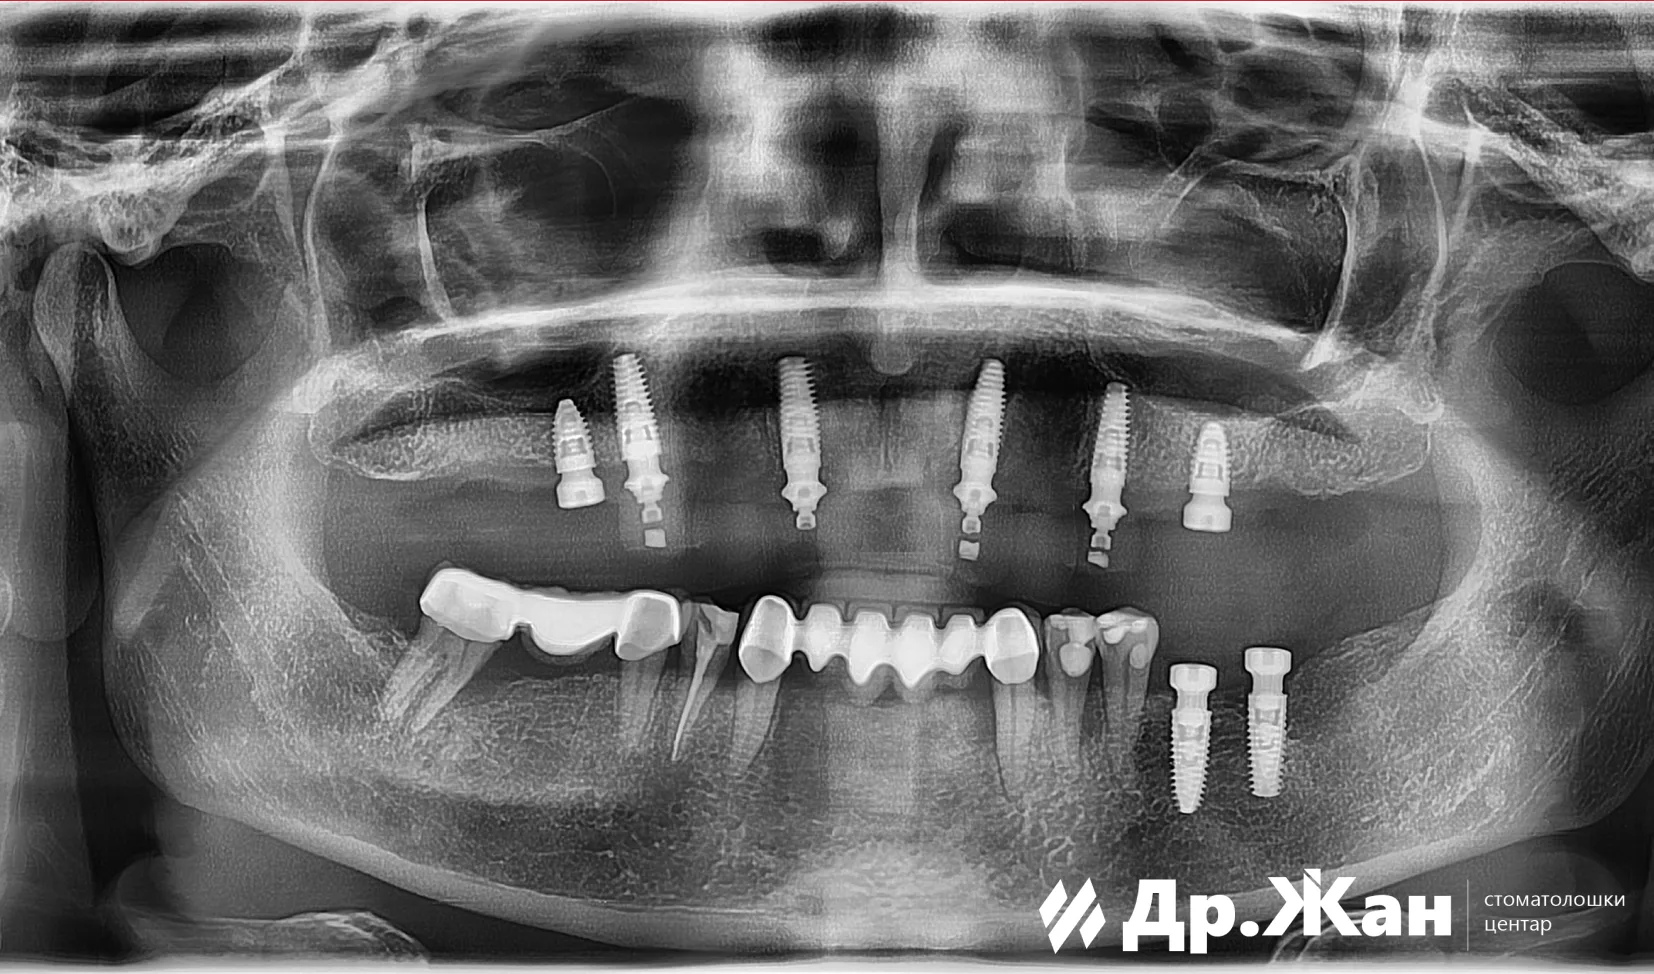

Ги извадивме сите заби и веднаш ги поставивме шесте импланти во горната вилица и уште два импланти во долната вилица. Имплантите беа поставени со помош на дигитален хируршки водич за импланти за најдобар можен резултат на позиционирање на имплантот. На пациентката веднаш ѝ обезбедивме привремени заби.

ПОТОА

По 4 месеци направивме прекрасна нова насмевка користејќи хибридна конструкција од цирконија на титаниумска шипка за долготрајна насмевка со најдобра можна естетика. Весна беше навистина среќна за нејзината нова насмевка и планираме подоцна да ги промениме долните коронки за да можеме да постигнеме уште поубава насмевка.